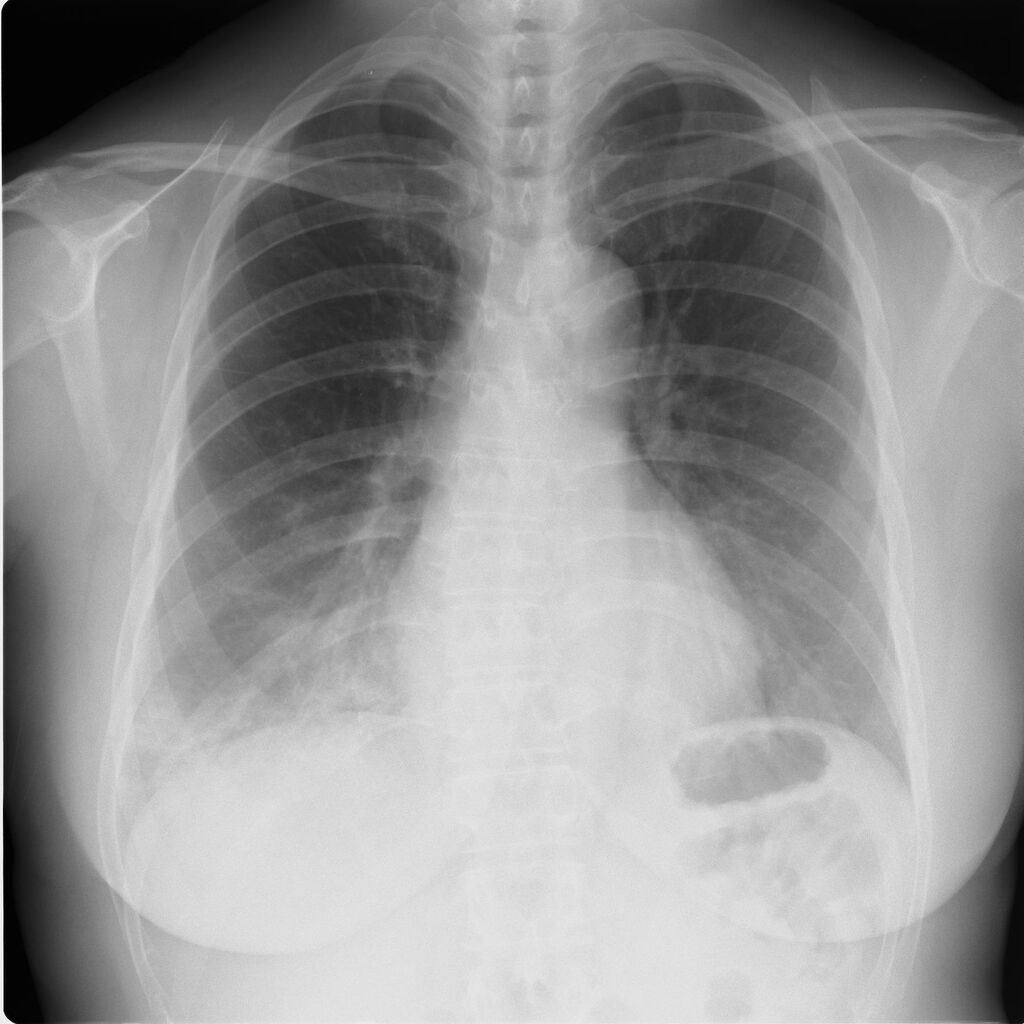

30代、高熱続き4日目酸素飽和度88%(COVID-19中等症)